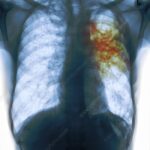

TB Diagnosis

Diagnosing tuberculosis (TB) requires a combination of clinical evaluation and diagnostic tests. If a person shows symptoms or has been exposed to someone with TB, a healthcare provider will conduct a detailed physical examination and review their medical history. Common initial tests include the tuberculin skin test (Mantoux test), which measures the body’s immune response to TB bacteria, and the interferon-gamma release assay (IGRA), a blood test that detects TB infection. If results suggest TB, additional investigations such as chest X-rays, sputum analysis, or CT scans are done to confirm active disease and assess its severity. Early and accurate diagnosis is vital for starting timely treatment and limiting the spread of TB.